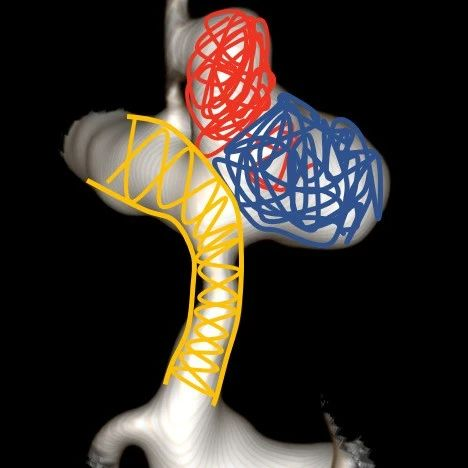

治疗策略: 瘤内栓塞-血管成形-支架释放

6. 考虑到血管条件较差,操作相对较多,需要足够的支撑力,我们需要采用Transend长交换导丝,使整个系统走到足够远。支架方面,我们决定选用新上市的Enterprise 2来兼顾“成形”与“脚手架”的双重作用。看看新一代的Enterprise在这个案例上表现如何。

7. 选择好工作角度,开始!对于这类的分叶状(或者有子瘤的“葫芦状”)动脉瘤,我们一般采用分部填塞的方式,以期达到瘤囊内的致密填塞。

载瘤动脉严重狭窄,必须要扩张,然而动脉瘤相对宽颈,载瘤动脉扩张前致密裸栓可能性不大,所以子瘤也要尽量致密栓塞,减少扩张载瘤动脉血流冲击增多后动脉瘤的出血可能性!

而对于第三种,我们完全可以把它视为两个动脉瘤,分别做致密填塞

8. 填到瘤颈,这里有一点小Tips:对于这样的案例,我们可以利用微导管或微导丝的弓形来作为弹簧圈的“支撑”,从而进行瘤颈部的处理,这种方法同时保证本就纤细的载瘤动脉的通畅度,而不增加额外操作。事实上,韩国和欧洲原来也有相似技术的文献报道,效果很好。在这里,我们使用确保远端通路的SL10作为支撑导管,Headway 17作为填塞导管,实现了瘤颈部致密填塞。

微导管保护下填塞瘤颈

注:红色箭头为Coiling: Headway 17 Mc,蓝色箭头为Protecting: SL 10 Mc。

微导管/微导丝保护技术

9. 后面的工作就相对轻松了,2.75的Gateway成形后,我们可以看到动脉瘤内弹簧圈已经足够致密,于是撤下弹簧圈微导管,更换为Prowler Plus,释放支架。Enterprise 2顺利释放新的Enterprise的网孔波幅更大,能够在血管外弧充分延展,血管内弧足够压缩,从而获得良好的贴壁性。

球囊扩张-支架释放